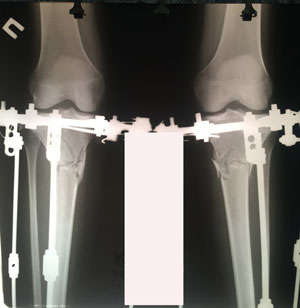

Дома на сращении

71 день с момента операции